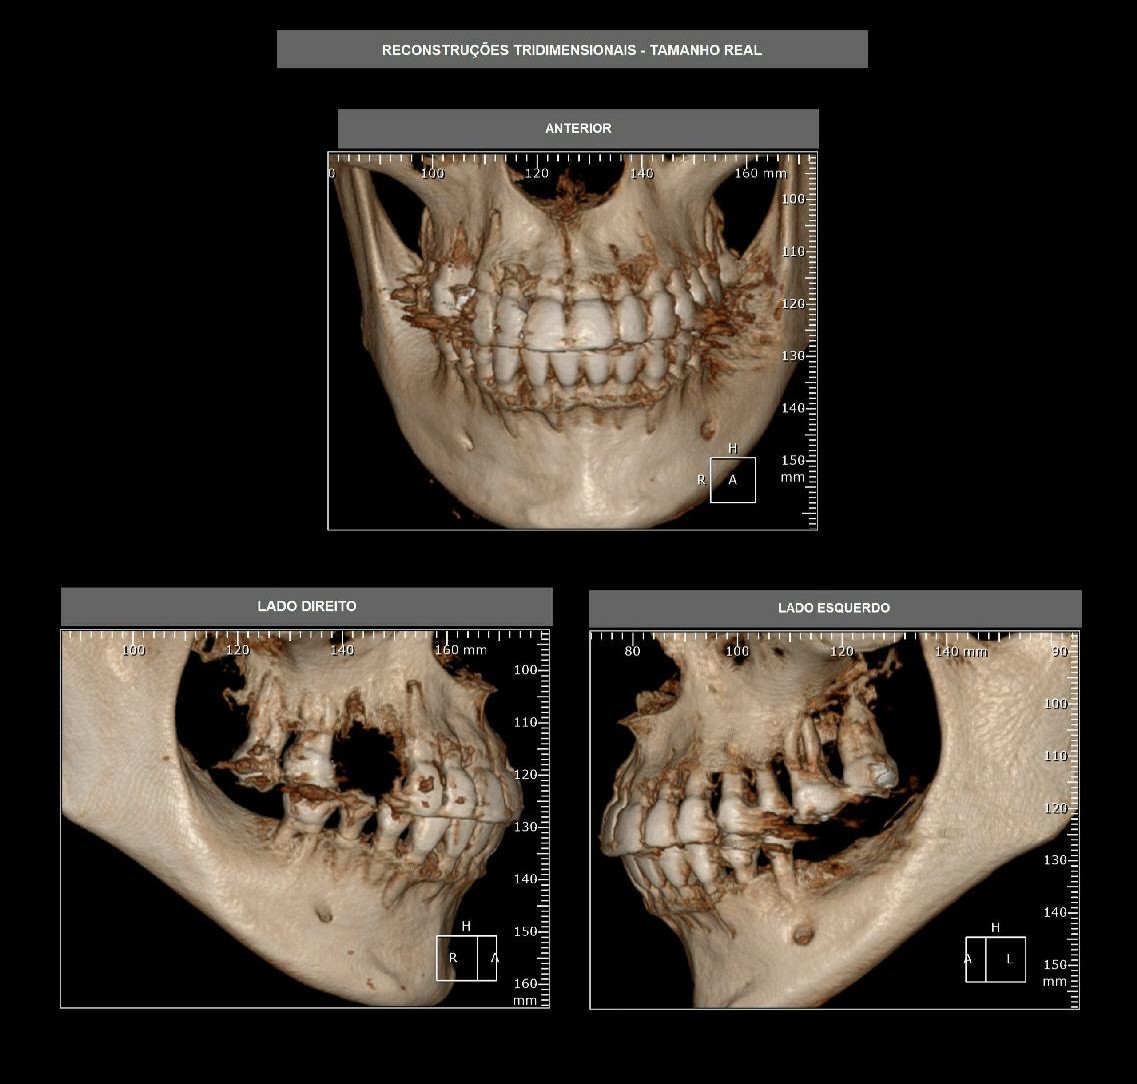

Radiologia Forense e sua Importância nas Investigações Médicas Legais. Publicado: N°2-2024 Con – Ciencia Forense: Convergencia de Disciplinas: Aplicaciones Forenses y Jurídicas 1. Introdução A Radiologia Forense teve início com o Prof. Arthur Schuster do Owens College que já em …

O papel fundamental dos tecnólogos e técnicos em Radiologia nas investigações Forenses Recebido: 21/12/2023 | Revisado: 28/12/2023 | Aceitado: 29/12/2023 | Publicado: 02/01/2024 Resumo A Radiologia Forense é uma área da medicina legal que utiliza técnicas de imagem para investigar …